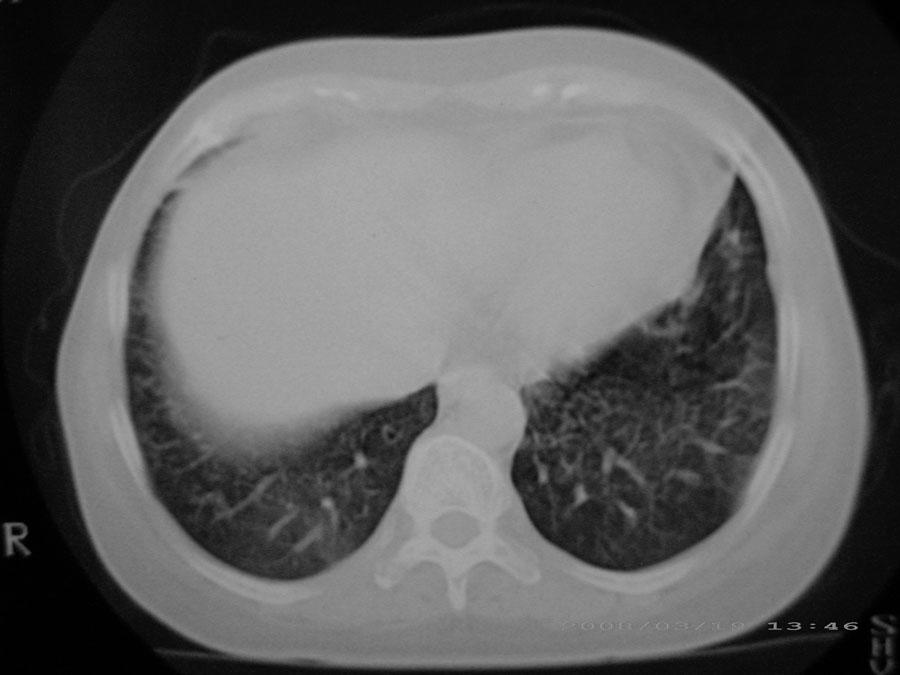

标题: CT13104:胸部大家看看啊,第一次发啊, [打印本页]

标题: CT13104:胸部大家看看啊,第一次发啊,

粟粒性结核

细支气管肺泡癌

本病例主要是癌性淋巴管炎与结节病的鉴别。好好查查吧。

密漫性沿纹理走行小结节影;有间质纤维化;可考虑尘肺;以图而论

血行播散性肺结核

双肺网状结构,小叶间质结节状增厚,考虑结节病

综合大家意见,结核、结节病、肺泡细胞癌均有可能,间质性肺炎暂不考虑,病灶纠集不明显,纵隔未见钙化淋巴结,尘肺可能性不大,但还是要密切结合临床诊断。

今天重新仔细看了看,矽肺确实不能除外,病灶主要表现为间质结节及纤维化。好好问问病史吧。